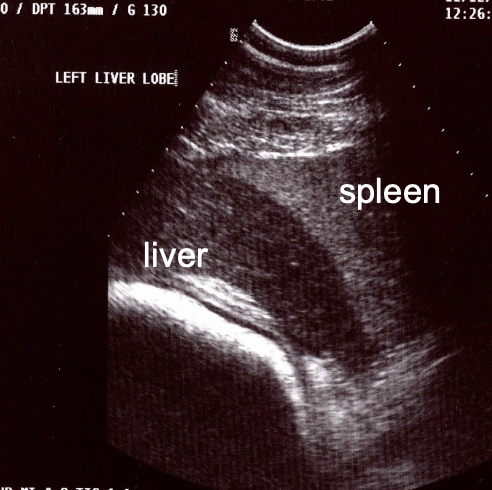

ultrasound

must know normals! (architecture, expected size, comparison to spleen)

where is the liver located on the left side of the horse?

7th-9th intercostal space

ventral to lung, next to spleen (usually ends at costochondral junction)

stable with age (unlike the right side)

what is the normal appearance of the liver on ultrasound?

-uniform

-sharp edges

-darker than spleen (left side)

-ends at or before costochondral junction (dont confuse with peritoneal fat)

-anechoic vessels visible

-no obvious biliary channels

-no shadowing structures